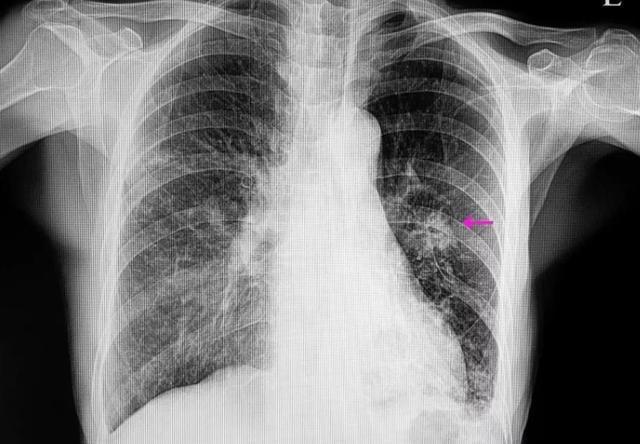

肺部小结节x光

肺部小结节x光,

体检发现肺部结节的人越来越多,胸部ct和胸部x线有什么区别?

左肺下野结节影,胸片建议ct!